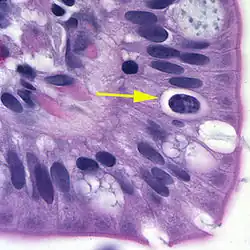

| Oocyst in epithelial cyst of mammalian host | |

At time of excretion, the immature oocyst usually contains one sporoblast (more rarely two). In further maturation after excretion, the sporoblast divides in two, so the oocyst now contains two sporoblasts. The sporoblasts secrete a cyst wall, thus becoming sporocysts; and the sporocysts divide twice to produce four sporozoites each. Infection occurs by ingestion of sporocyst-containing oocysts: the sporocysts excyst in the small intestine and release their sporozoites, which invade the epithelial cells and initiate schizogony. Upon rupture of the schizonts, the merozoites are released, invade new epithelial cells, and continue the cycle of asexual multiplication. Trophozoites develop into schizonts which contain multiple merozoites. After a minimum of one week, the sexual stage begins with the development of male and female gametocytes. Fertilization results in the development of oocysts that are excreted in the stool. Cystoisospora belli infects both humans and animals.

Microscopic demonstration of the large typically shaped oocysts is the basis for diagnosis. Because the oocysts may be passed in small amounts and intermittently, repeated stool examinations and concentration procedures are recommended. If stool examinations are negative, examination of duodenal specimens by biopsy or string test (Enterotest) may be needed. The oocysts can be visualized on wet mounts by microscopy with bright-field, differential interference contrast (DIC), and epifluorescence. They can also be stained by modified acid-fast stain.